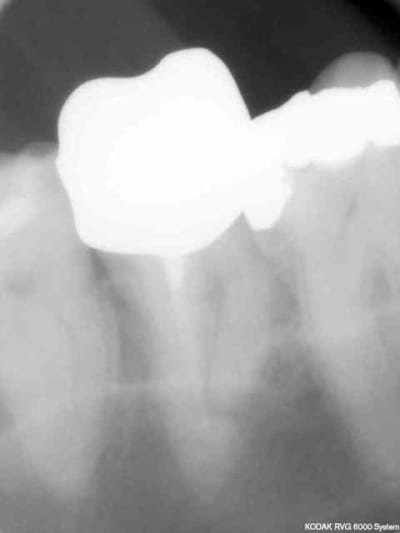

Endo 16 + sc 33. Costeaude la racine DV.

Capture d e cran 2015 07 30 15.33 - Eugenol